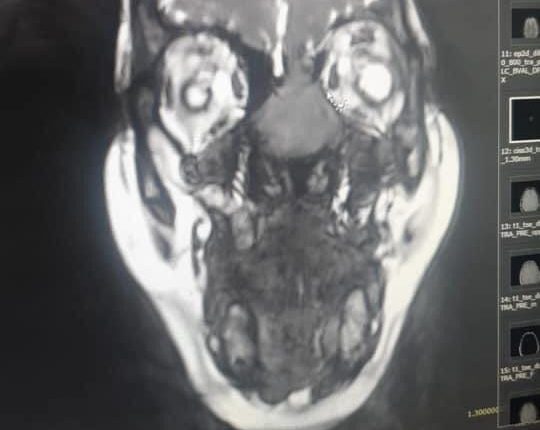

وأضاف الصفدي أن مثل هذه العمليات هي نتائج جهد مشترك من دائرة الأنف والأذن والحنجرة وأطباء الأشعة وفريق تخدير متخصص وكوادر تمريضية متخصصة ومؤهله.   وبين العقيد الطبيب نبيل الشواقفه انه في السابق أجريت للمريضة عملية لاستئصال الورم عن طريق فتح الأنف من الخارج وتم تشخيص الحالهrhabdomyosarcoma وبعد ذلك أخذت المريضة عدة جرعات من العلاج الكيماوي ولكن بعد فترة عادت المريضة تشكو من نفس الأعراض وبعد إجراء الفحوصات والأشعة اللازمة تبين وجود ورم دموي خبيث يملىء تجويف الجهة اليسرى من الأنف واختراقه للحاجز الأنفي مما أدى الى تآكل في عظم قاع الجمجمة وامتداد الورم بإتجاه الدماغ واتصاله بأغشية الدماغ الخارجية.

واضاف العقيد الطبيب الشواقفه أنه وبعد تشخيص الحالة تم إجراء استئصال للورم باستخدام المناظير الأنفية وبدون جروح خارجية وذلك بعد استحالة عمل قسطرة علاجية نظرا لخطورة هذا الإجراء وإحتمالية فقدان البصر وبناء على ذلك تم استئصال الورم جراحيا باستخدام المناظير وعمل رقع لقاع الجمجمة وتمت العملية بدون مضاعفات وآثار جانبية والحمدلله المريضة الآن تتماثل للشفاء وهي بصحةجيدة.